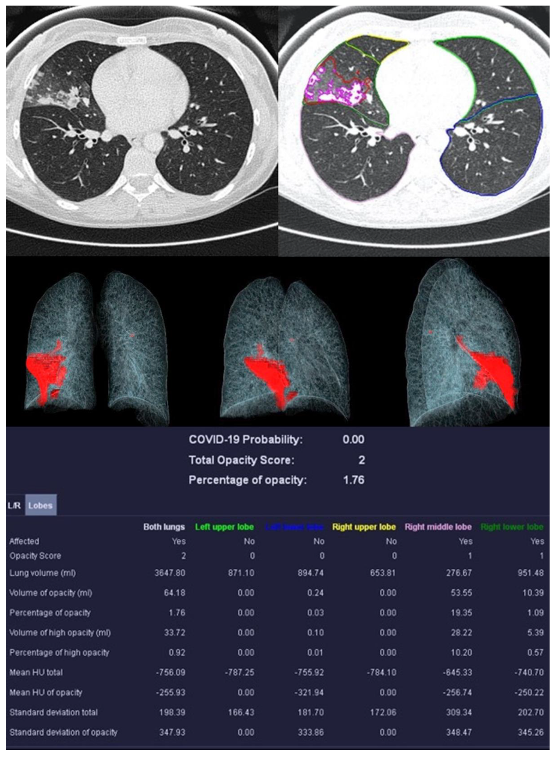

3.2. Image Analysis

| Mean COVID-19 Probability ± SD | 0.80 ± 0.36 | 0.33 ± 0.4 | 0.55 ± 0.47 | 0.66 ± 0.44 |

| Mean LSS ± SD | 8 ± 5 | 5 ± 4 | 5 ± 6 | 0 ± 0 |

| Mean PO ± SD in % | 26.39 ± 23.22 | 12.52 ± 17.97 | 18.90 ± 26.27 | 0.05 ± 0.12 |

| Mean PHO ± SD in % | 6.42 ± 7.68 | 3.60 ± 4.47 | 5.86 ± 10.04 | 0.01 ± 0.02 |